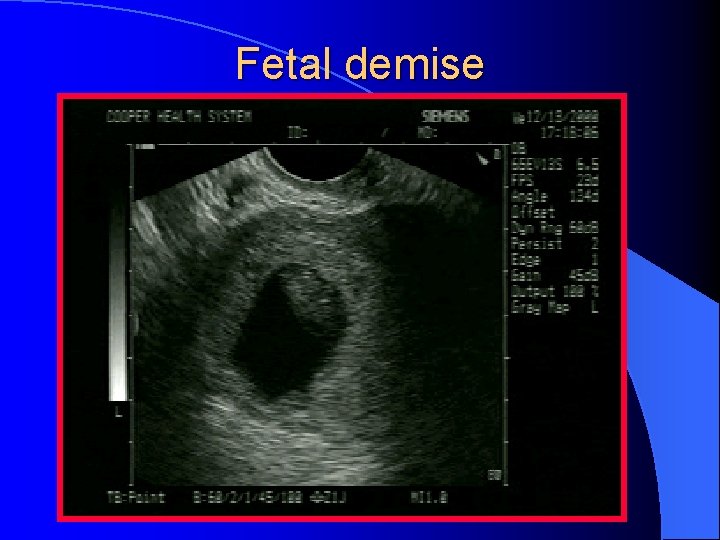

Fetal demise

A Fetal Heart Beat l An important prognostic indicator l The rate of spontaneous abortion is extremely low (2 - 4%) after the detection of normal embryonic cardiac activity l The normal fetal heart rate in early pregnancy is 112 -136

Abnormal IUP l. A GS larger than 10 -13 mm diameter(TV) or 20 mm (TA) without a yolk sac l A GS larger than 18 mm (TV) or 25 mm (TA) without a fetal pole l. A definite fetal pole without cardiac activity after 7 wks GA